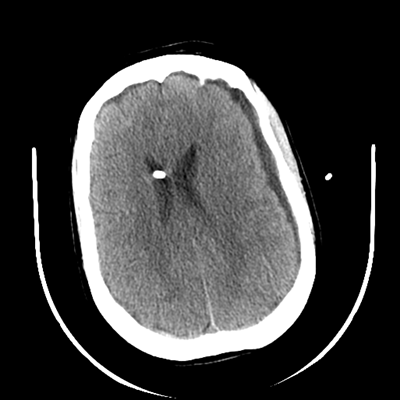

The patient goes down to CT. The following images are obtained. The subdural fluid collection is stable, as is the ventricular caliber.

NCHCT

Starting with the non-contrast head CT, we can appreciate that there's actually not much residual subarachnoid blood at all; it's essentially all resorbed already (and cleared through the EVD). The ventricular caliber is stable. With the CTA head (for convenience's sake, the MIPs were shown), it's subtle, but we can see that the PCAs on each side are not as smooth and regular. The right MCA, starting at the bifurcation, also becomes narrower. This is [radiographic] vasospasm. Now, looking at the CT perfusion-- specifically, the Tmax (MTT) map that were selected-- there's clearly some abnormality within the bilateral cerebellar hemispheres and occipital lobes. Not a lot, but it's there. Delving further into this map, we can appreciate that the areas of abnormality are mainly green, signifying that these areas have Tmax > 6 seconds. This is the threshold that is specific, not sensitive, for vasospasm.

Yes! It does. The patient had a decline in level of consciousness with diffuse loss of motor function. This does correlate to the basilar territory. (Alternatively, bilateral MCA vasospasm could also be responsible, reminding us that a decline in consciousness could technically be focal/multifocal.) Thus, we can say that this patient does have clinical vasospasm. Whether this will develop into irreversible DCI remains to be seen; at least, the non-contrast head CT and the other portions of the CT perfusion (not shown) currently don't [yet] suggest infarction.